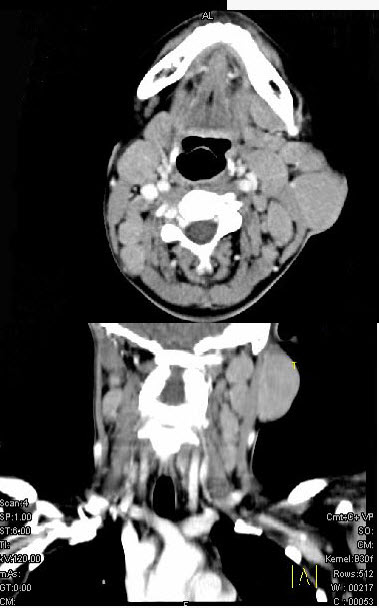

女,25岁、发现双侧颈部肿块近10年,CT如图,最可能的诊断为()。

A、巨淋巴结增生症

B、淋巴瘤

C、转移癌

D、淋巴结结核

E、淋巴结炎

A